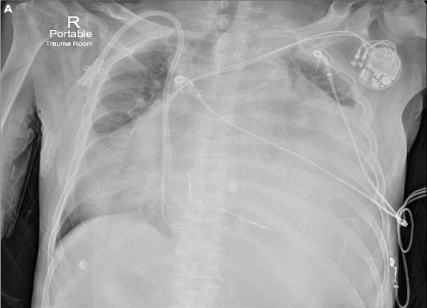

A 76-year-old man with end-stage renal disease on intermittent hemodialysis was brought to the emergency department with a one-week history of fatigue and exertional dyspnea. On initial assessment, his blood pressure was 134/90 mmHg, heart rate was 76 bpm and oxygen saturation was 78% on ambient air. Other findings included an elevated jugular venous pressure, distant heart sounds and absent air entry throughout the left lung field. Chest X-ray (Figure 1A) revealed nearly complete opacification of the left hemithorax with contralateral tracheal deviation. Shortly thereafter, he became hemodynamically unstable. Immediate bedside ultrasound demonstrated a large pericardial effusion with evidence of tamponade, including diastolic collapse of the right atrium and right ventricle. Urgent pericardiocentesis was successfully performed to stabilize the patient. A subsequent CT chest (Figure 1B) demonstrated a massive pericardial effusion causing complete collapse of the left lung. In total, 4.3L of fluid were drained, resulting in re-expansion of the left lung and hemodynamic stabilization. Twenty-four hours later, a transthoracic echocardiogram demonstrated a residual posterior effusion with no evidence of cardiac tamponade. Repeat chest X-ray (Figure 2) demonstrated improved aeration of both lungs with residual pericardial effusion and atelectasis. Tests for malignancy, infection and tuberculosis were negative. Despite regular hemodialysis, the effusion reaccumulated one month later, requiring a repeat pericardiocentesis.

Figure 1A. Portable chest X-ray demonstrates nearly complete left hemithorax opacification with opacity extending into the right hemithorax. A haemodialysis line and dual-lead pacemaker are also present